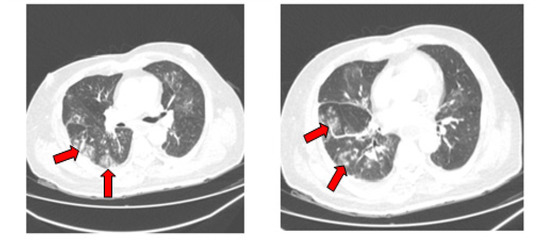

| Age | Sex | Type of AL | Initial Thoracic CT Scan | Control Thoracic CT Scan | GM Serum | IgM Anti-Aspergillus Antibodies | COVID-19 Outcome | Final Outcome | |

|---|---|---|---|---|---|---|---|---|---|

| P1 * | 55 | Female | AML | Widespread GGOs | complete regression | Positive | Positive | Recovered | Alive |

| P2 * | 56 | Female | AML | Widespread GGOs | complete regression | Positive | Positive | Recovered | Dead |

| P3 * | 34 | Male | APL | Widespread GGOs | complete regression | Negative | Positive | Recovered | Alive |

| P4 * | 58 | Male | AML | Widespread GGOs | incomplete regression | Negative | Positive | Recovered | Alive |

| P5 * | 37 | Male | AML | N/A5 | N/A | Negative | Positive | Recovered | Alive |

| P6 * | 58 | Male | AML | GGOs in inferior lung lobes | incomplete regression | Negative | Positive | Recovered | Alive |

| P7 * | 27 | Female | AML | GGOs in inferior lung lobes | complete regression | Positive | Positive | Recovered | Alive |

| P8 * | 26 | Male | ALL | Widespread GGOs | incomplete regression | Positive | Positive | Recovered | Alive |

| P9 * | 53 | Male | AML | Widespread GGOs | complete regression | Positive | Positive | Recovered | Alive |